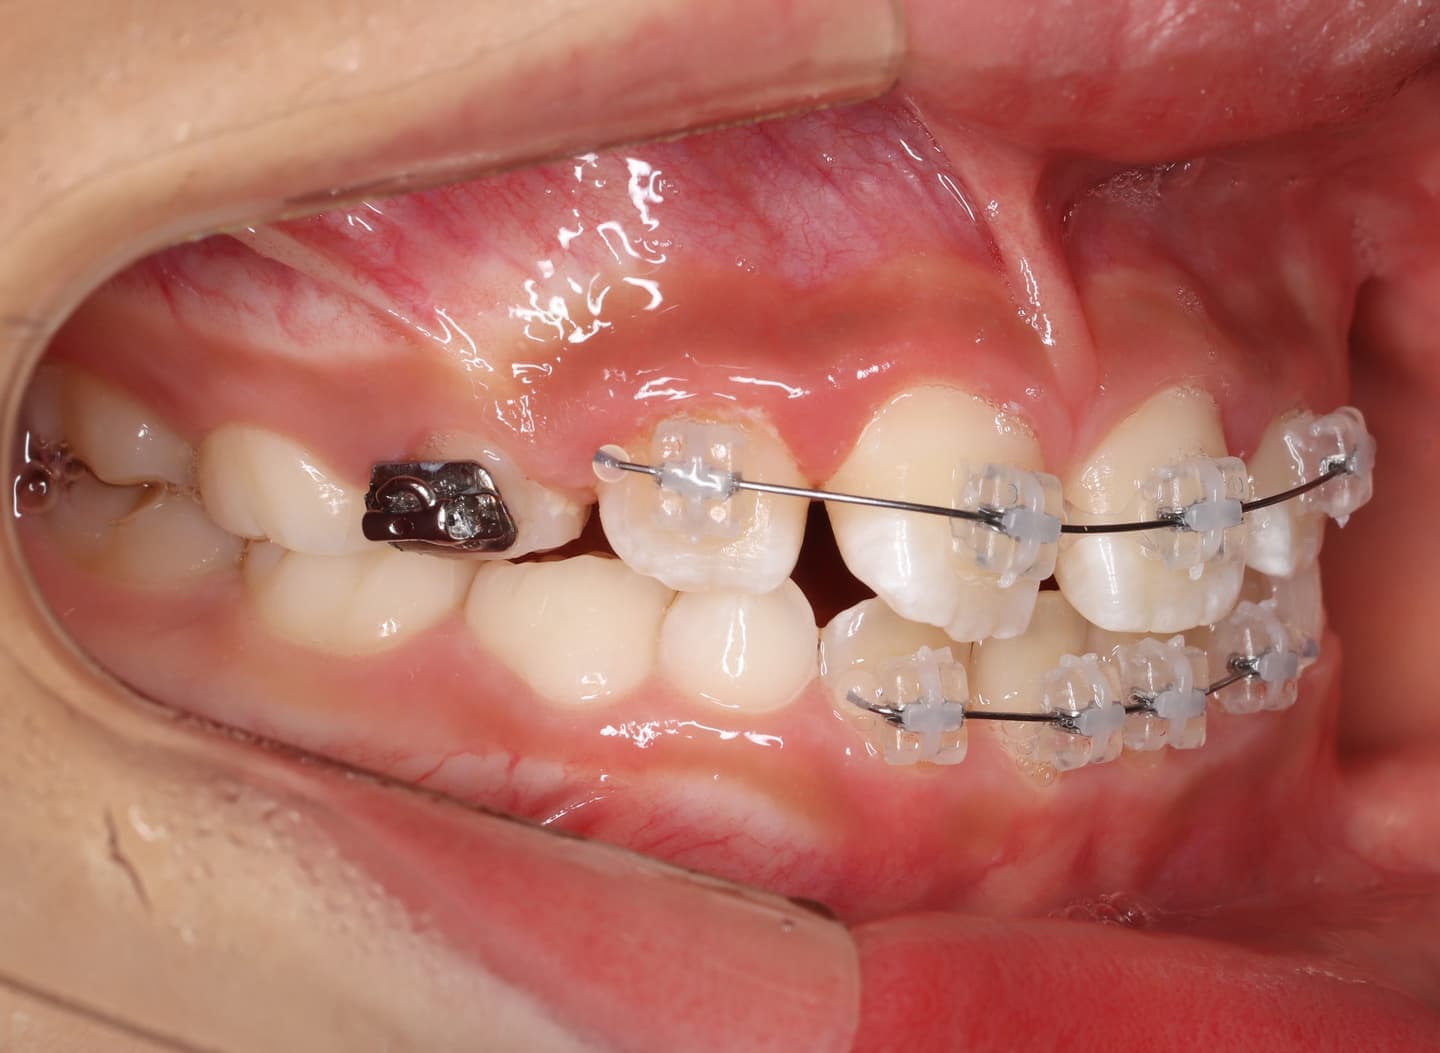

治療法:拡大プレート+フルパッシブブラケット(クリアスナップ)

治療後(12ヶ月後)

治療中